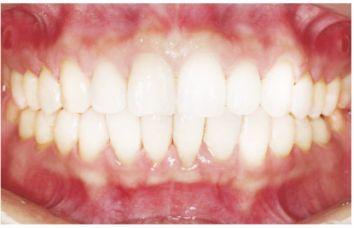

種植修復(fù)后照片

這一位老先生則選擇了All-on-4種植技術(shù),即拔即種,上下頜分別種植4個(gè)植體就完成了全口牙齒修復(fù),費(fèi)用降低了不少,而且創(chuàng)傷小,恢復(fù)快。